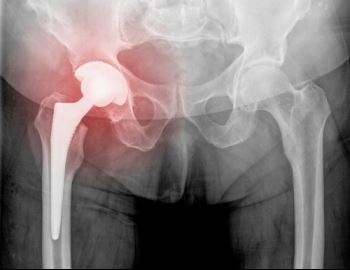

X-ray result

Car accidents tend to be overwhelming and traumatic events, even in cases when the circumstances might not appear to be serious. All types of accidents, from fender-benders to large-scale crashes involving multiple motor vehicles, can result in a variety of injuries, including soft tissue injuries, traumatic brain injuries, lacerations, and internal hemorrhaging. Some injuries are obvious and immediately apparent, but some are not as pronounced. In fact, a person might have suffered a severe injury without even knowing it until days, weeks, or even months later. If the side effects of your injuries are delayed, what should you do?